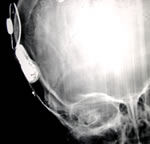

This is how we hearA Cochlear Implant or a Bionic Ear is an electrical device intended to restore a level of auditory sensation via direct electrical stimulation of the hearing nerve to help profoundly deaf individuals who gain little or no benefit from hearing aids.

Environmental sounds are picked up by a microphone that is behind the ear, converted into an electrical signal and are passed through a speech processor, which codes it into a pattern of electrical pulses. Through a coil the speech processor then sends this code to the implant, which is surgically implanted under the scalp. The implant transmits this code to the electrodes implanted in the cochlea where the auditory nerve picks it up and passes it to the auditory cortex in the brain. The brain recognizes this code as sound.

A cochlear implant is surgically inserted in the cochlea through an ear surgery under general anaesthesia.